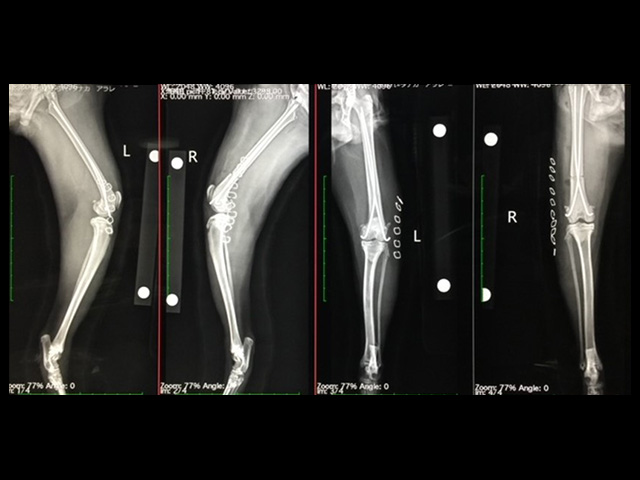

① 橈尺骨骨折

近年増加傾向にあるトイ種の橈尺骨骨折は、転落などの原因により、同骨の遠位に生ずることが多く、中でも手根関節(手首)近くでの骨折は、整復後の安定化が困難なために難治性骨折に位置付けられています。また、動物の前肢はヒトのそれと異なり荷重肢であるため、安定した初期固定が必要です。特に若齢犬や小型で骨が小さい場合には、1.0mm~1.5mmのスクリューを使用する小型のプレートが必要となります。